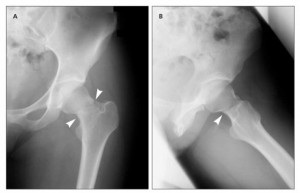

Συμπτώματα κατάγματος του μηριαίου οστού

Οι περισσότεροι ασθενείς με κάταγμα του μηριαίου αισθάνονται πόνο στο πρόσθιο μέρος της βουβωνικής χώρας κατά την στάση και κίνηση. Η βάδιση είναι εξαιρετικά δύσκολη και η άσκηση σχεδόν πάντα είναι αδύνατη. Τα περισσότερα κατάγματα του μηριαίου, χρειάζονται χειρουργική επέμβαση.